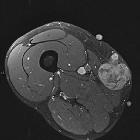

CT

- generally heterogeneous

- commonly demonstrate central low attenuation representing necrosis

- calcification exceedingly rare

MRI

The tumor frequently demonstrates cystic foci. Signal characteristics include

- T1: isointense to muscle

- T2 non-fat suppressed: intermediate to hypointense to neighboring fat

- T2 FS: predominantly hyperintense